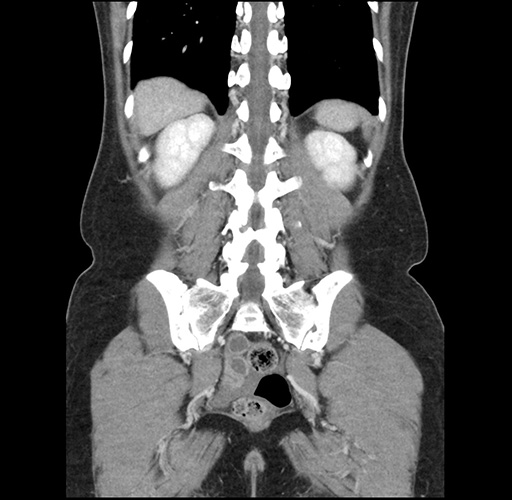

Imaging Analysis

Look through the patient's CT scan to identify any areas of concern for the necessary procedure.

Based on your CT findings, which issue(s) would give reason for "planned slowing down moment(s)" in this case?

Considering a standard left lateral sectionectomy procedure, what step(s) of the operation would you do differently in this case ?